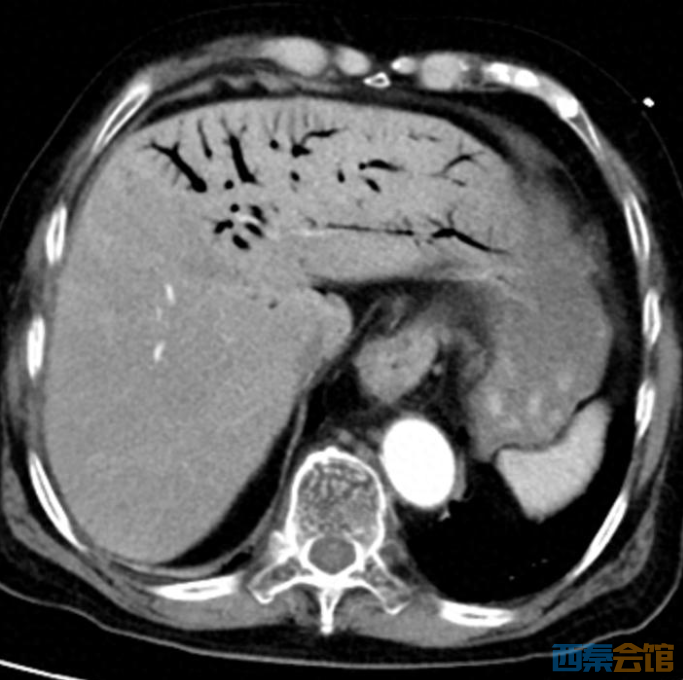

平时的剩菜、剩饭,一些人舍不得倒,习惯放冰箱里,到时候“热一热再吃”。但冰箱不是食物保险箱,食物保存不当或者放久了食用,会致病,甚至会危及生命。 近日,临海市第二人民医院ICU接诊一位76岁患者,只因吃了冰箱冷藏4天的鸡肉,突发休克、肝脏里布满气体,被医生判定为“死神之征”。 凶险急症: 肝门静脉积气 医学上的“死神之征” 当晚10点,76岁李大伯被家人紧急送入临海市第二人民医院急诊,他大汗淋漓、腹部僵硬如石。据家人说,李大伯从下午4点开始腹胀腹痛,症状持续加重。 急诊CT结果让医护人员高度警惕:肝门静脉及肠系膜静脉广泛积气。

肝脏内血管广泛积气

腹胀明显,肠道积气